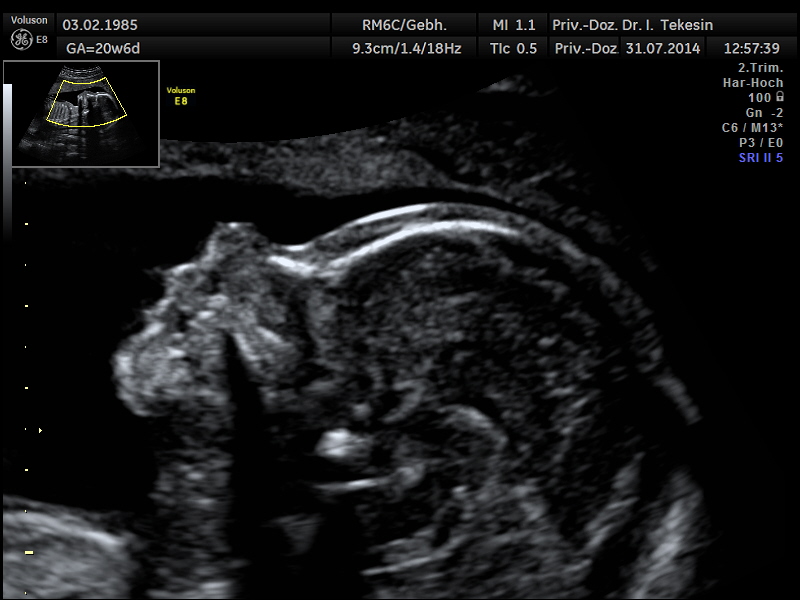

ULTRASCHALLFEINDIAGNOSTIK >>>

Die Ultraschalluntersuchung ist ein bildgebendes Verfahren, das nach heutigem Kenntnisstand selbst bei wiederholter Anwendung keine Schäden bei Mutter und Kind verursacht. Eine Ultraschallfeindiagnostik können wir Ihnen optimal zwischen der 20. und 22. SSW anbieten.

Eingehende Ultraschalluntersuchung

Diese Untersuchung ist wesentlich umfangreicher als der gemäß den Mutterschaftsrichtlinien vorgesehene Ultraschall in diesem Zeitpunkt. Neben speziellen Geräten erfordert er auch große Erfahrung des Untersuchers.

Entscheidende Rolle bei dieser Untersuchung spielt die Lage des Kindes und die Stärke der mütterlichen Bauchdecken. Dabei betrachten wir alle darstellbaren Organe und Merkmale des Ungeborenen: das altersentsprechende kindliche Wachstum, die Fruchtwassermenge, das Aussehen und die Funktion aller sichtbaren Organe und die Lage und das Aussehen der Plazenta.

Profil in der 21. Woche

Profil in der 25 Woche